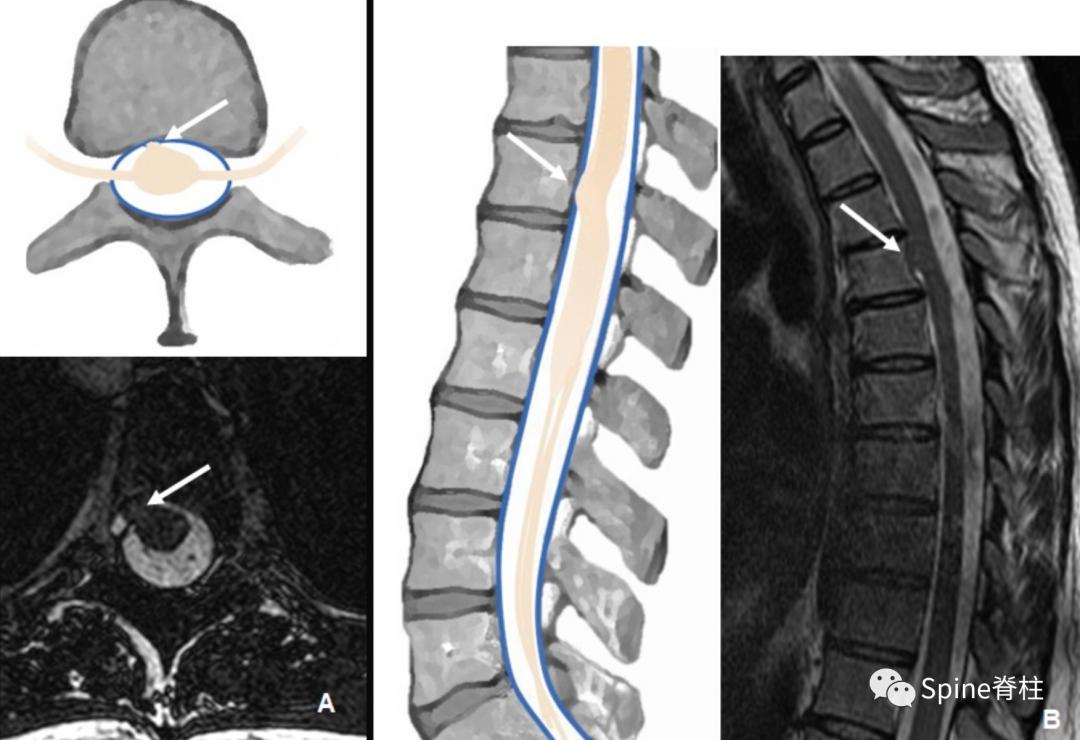

1.2 神经根袖憩室 Diverticula of root sleeves

历史上称为神经根旁囊肿或 Tarlov 囊肿,这些囊性病变在硬膜和周围神经鞘之间的过渡处与蛛网膜下腔相通。它们可能包含感觉神经根,但多数无症状,累及腰骶部可累及数个神经根 (下图)。

一名73岁左臀部疼痛5个月患者。模式图提示根袖憩室(神经根旁囊肿)的典型外观(A)。黑箭头为通过硬膜缺损的蛛网膜突出。横断面和矢状面T2加权像提示左侧S1神经根袖囊肿,注意神经根的位置,粘附在囊壁(白色箭头,图B和C)

一名58岁患者,有 5 个月车祸后进行性脊髓病病史。 模式图提示硬膜内外层之间的囊肿的典型外观(A) 。矢状位 (B) 和横断面 (C) 颈椎MPR FIESTA MR图像提示从C4-T1硬膜撕裂,但不伴有脊髓疝

当这些硬膜内外层之间的囊肿与脊髓疝相关时,应考虑先天性或退行性改变。脊髓疝可导致进行性脊髓病,引起脊髓半切综合征Brown-Sequard综合征。在这种情况下,硬膜缺损可以通过MRI很容易定位,因为疝的位置标志着缺损部位(下图)。

一名50岁硬膜撕裂伴脊髓疝患者。模式图和横断位T2加权像提示T4水平脊髓前移(A)。FIESTA图像(B)提示脊髓伴右侧腹外侧硬膜突出(箭头)